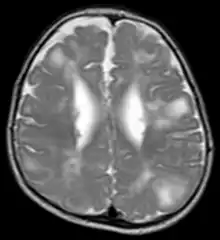

Classic intracranial manifestations of TSC include subependymal nodules and cortical/subcortical tubers.[11]

The tubers are typically triangular in configuration, with the apex pointed towards the ventricles, and are thought to represent foci of abnormal neuronal migration. The T2 signal abnormalities may subside in adulthood, but will still be visible on histopathological analysis. On magnetic resonance imaging (MRI), TSC patients can exhibit other signs consistent with abnormal neuron migration such as radial white matter tracts hyperintense on T2WI and heterotopic gray matter.

Subependymal nodules are composed of abnormal, swollen glial cells and bizarre multinucleated cells which are indeterminate for glial or neuronal origin. Interposed neural tissue is not present. These nodules have a tendency to calcify as the patient ages. A nodule that markedly enhances and enlarges over time should be considered suspicious for transformation into a subependymal giant cell astrocytoma, which typically develops in the region of the foramen of Monro, in which case it is at risk of developing an obstructive hydrocephalus.

A variable degree of ventricular enlargement is seen, either obstructive (e.g. by a subependymal nodule in the region of the foramen of Monro) or idiopathic in nature.